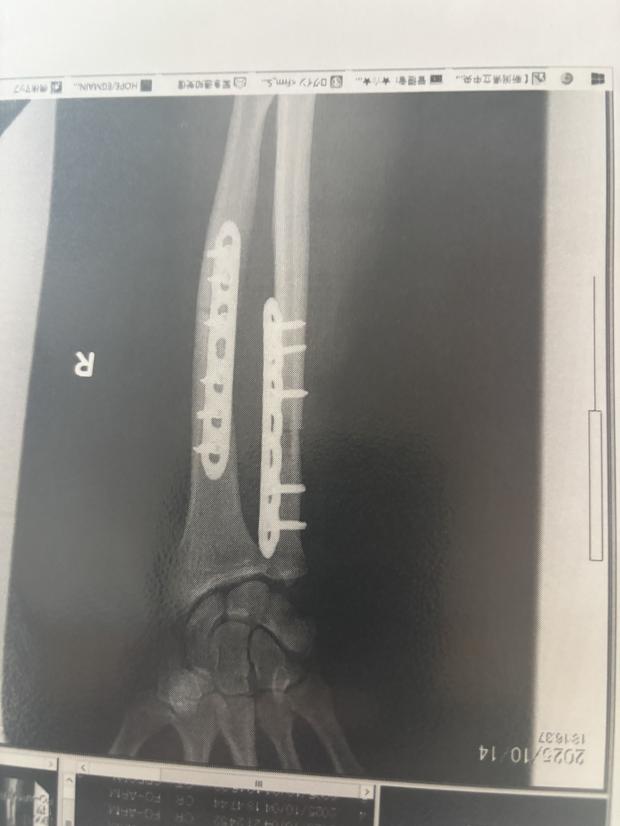

De la atacul ursului până în prezent, ultramaratonistul a trecut prin trei intervenții chirurgicale. Acestuia i s-a efectuat un transplant de os de șold, pentru a acoperi o bucată din osul mușcat, și i s-au montat plăci metalice în braț. Acum, Halloran este în etapa de recuperare.